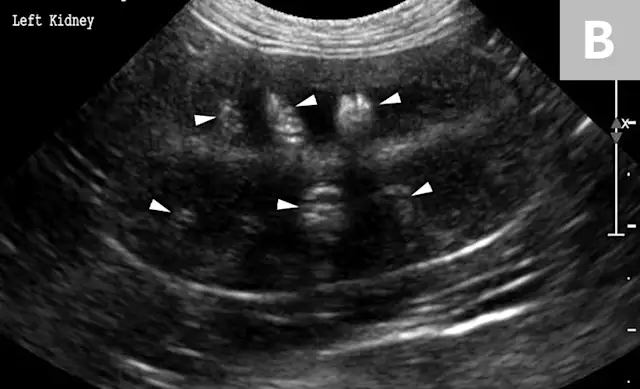

Clinical signs associated with ureteral calculi may range from chronic non-specific signs to acute or chronic renal failure. The presence of hydronephrosis can be highly suggestive of a ureteral obstruction (Figure 6).

FIGURE 6A

Mild to moderate right hydronephrosis and proximal ureteral dilation in a Dalmatian.